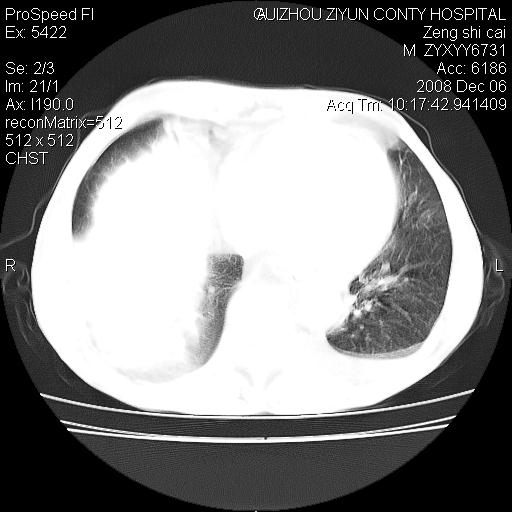

标题: CT16961:M、71岁,咳嗽半年,无血痰;胸片示右肺占位。 [打印本页]

标题: CT16961:M、71岁,咳嗽半年,无血痰;胸片示右肺占位。

右肺纵隔型肺癌伴纵隔淋巴结转移!双侧胸水!

1)考虑右肺上叶纵隔型肺癌伴纵隔淋巴结转移。2)心包积液,双侧胸腔积液。

右肺上叶纵隔型肺癌伴纵隔淋巴结转移。心包积液,双侧胸腔积液。

右肺纵隔型肺癌伴纵隔淋巴结转移!双侧胸水\\心包积液